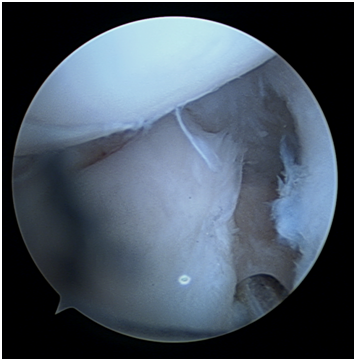

Figure 4 Arthroscopic view of pseudarthrosis.

The arthroscopic procedure started with the realization of standard radio-carpic initial portals; medium-carpal portals helped with the identification of the pseudarthrosis focus (Figure 4). The pseudarthrosis focus was blown out (Figures 5 & 6). The spongious graft of the contralateral iliac crest was harvested. Placement of the graft through the midcarpal portal of visualization by adapting the arthroscopy trocar (Figures 7-9). The traction was withdrawn. The graft was fixated with a percutaneous anterior approach and arthroscopic support and placement of the double compression screw with radiographic support (Figure 10).